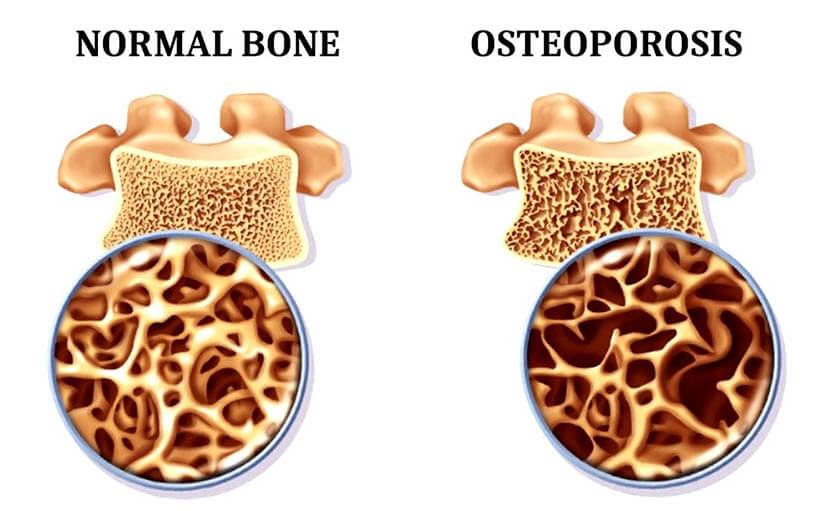

হাড়ক্ষয় প্রতিরোধে ক্যালসিয়াম | কেন হয় অস্টিওপরোসিস, করণীয় কী?

0 SHARES Share Tweet হাড়ক্ষয় প্রতিরোধে ক্যালসিয়াম যে বিশেষ ভূমিকা রাখে তা কতটুকু জানেন? এ নিয়ে বিস্তারিত জানানোর পূর্বে...